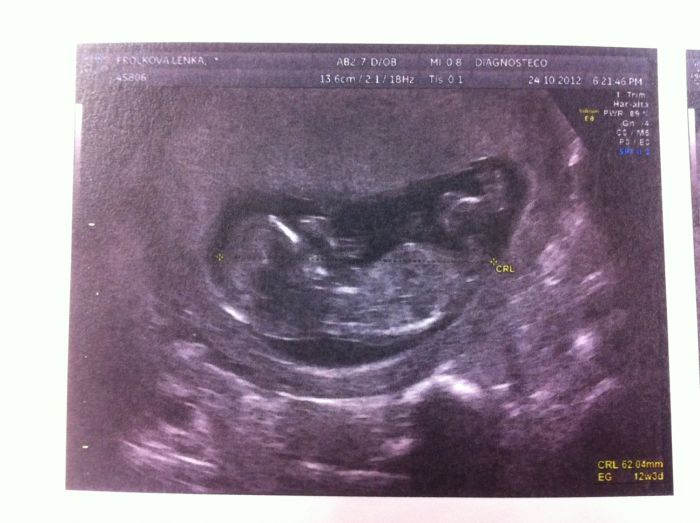

Utz a screening dopadl dobre. Riziko DS 1 : 26 000 a ostatnich 1 : 100 000 zbytek krve v poradku. Podle posledni MS jsem vcera byla 12+0 ale podle UTZ uz 12+3. Meril 6.2 cm a na 95 procent je to chlapecek. Takze co se tyce myho pruzkumu ( jestli si vzpominate ) tak moje intuice fungovala na 100 %. Prali jsme si devcatko, ale citila jsem ze to bude chlapecek. Jsem moc rada, ze je v poradku a treba podruhe nebo do tretice to budou holky ;). Musim si nejak zvyknout, ze budu mit chlapecka no ;).

Jinak, podle nosanku je do manzela a taky jsem hned volala nasim, ze ma ,, dlouhy noziska jak muj tatka, coz je cahoun ;),, Tak jsem videla na tatkovi dojeti ;). Je to jeho prvni vnoucatko.

Taky jsme si dokoupili dvd, stalo 10 E. Budu se Vam ted snazit poslat fotecku.

Holky, taky sse Vam zdaji ty nozicky tak dlouhy ;D??? Nebo jsem proste skrabla?